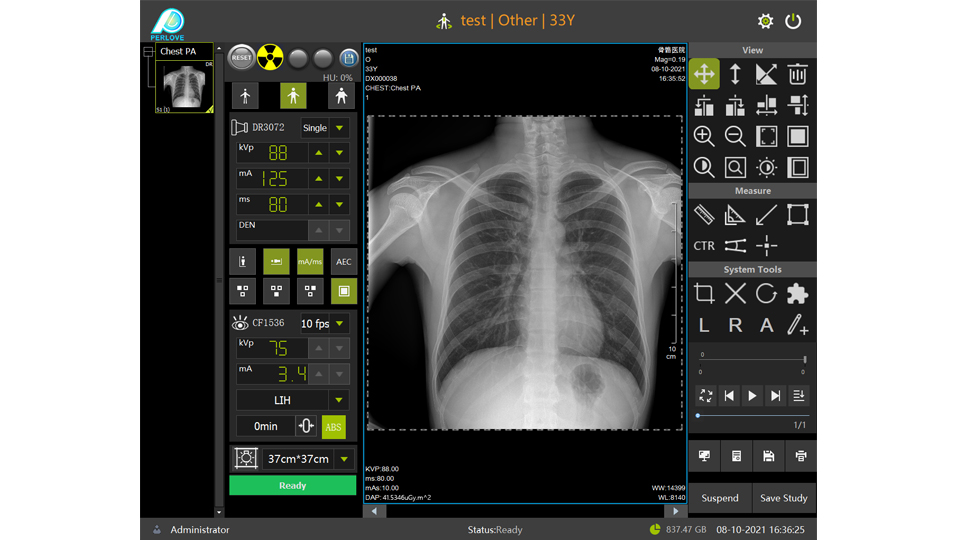

PLD6500系列是普利德研发的医用数字X线摄影机,采用双立柱结构,可供各级医院放射科对头部、胸部、腹部、腰椎、四肢等部位进行立位、卧位、正位、侧位的数字摄影检查。

● 人体图像化模型

搭配直观的人体图像化系统,一键调整曝光参数。

● 自动曝光控制

无需手动调节,系统自动控制射线剂量,获得适当的感光量。